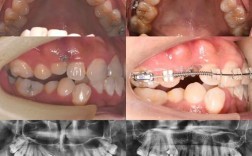

隐形矫正的核心在于“数字化精准控制”与“持续轻力移动”,医生通过口内扫描仪或传统取模获取患者牙齿的原始数据,结合口腔X光片、面部照片等资料,利用3D数字化技术建立患者的牙齿模型,随后,通过专业正畸软件模拟牙齿在矫正过程中的移动轨迹,将整个矫正阶段拆分为多个步骤(通常每步间隔0.25-1mm),为每个步骤定制一副透明牙套,患者需按顺序佩戴牙套,每副牙套通过材质自身的弹性对牙齿施加持续、温和的力,引导牙齿逐步移动至理想位置。

个性化与可视化:通过3D模拟技术,患者可在矫正前直观看到牙齿移动过程及最终效果,与医生共同调整方案,增强治疗信心;针对复杂病例,还可结合附件(牙面上的小凸点,辅助牙套固定牙齿)、橡皮筋等工具,实现精准控制。

初诊检查与方案设计:患者首次就诊时,医生会进行口腔检查、拍X光片(全景片、头颅侧位片)、取模或口扫,评估牙齿、颌骨、牙周状况,若符合适应症,医生将利用3D软件模拟矫正过程,确定治疗周期(通常1-3年)及最终效果,与患者沟通并确认方案。